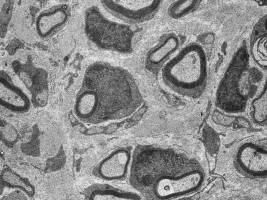

Gliazellen bilden nach einer Nervenschädigung das Protein Neuregulin1 und fördern so die Regeneration von Nervengewebe Das periphere Nervensystem besitzt im Gegensatz zum Gehirn und Rückenmark eine erstaunliche Regenerationsfähigkeit nach Verletzungen. Forscher am Max-Planck-Institut für experimentelle Medizin in Göttingen haben herausgefunden, dass periphere Gliazellen nach einer Nervenschädigung den Wachstumsfaktor Neuregulin1 produzieren, der einen wichtigen Beitrag zur Regeneration verletzter Nerven leistet.